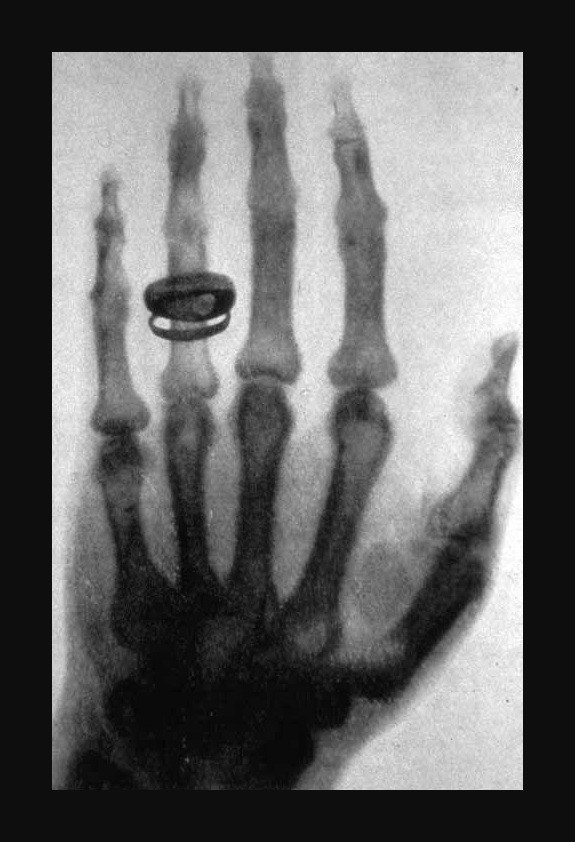

Photographie Röntgen im Dienste wissenschaftlicher Forschung (najvjerojatnije) Prva “električna” slika.

Na većini internetskih postova, a i u dostupnoj literaturi (tiskovinama) uz ovu sliku je potpisan tekst:

“Pretpostavlja se da je na toj (prvoj električnoj fotografskoj) slici ruka gospođe Röntgen.”

Postoji i jedna druga priča koja govori o tome da je ta slika nastala na promotivnom prikazivanju djelovanja Röntgenovih X-zraka u Opatiji, na samom početku XX stoljeća.

Naime tada, u tom mondenom okupljalištu aristokracije austrijskog Carstva, gospodin Röntgen je probranoj publici predstavljao svoje otkriće, na kojem je iz publike pozvao volontera voljnog da se izloži fotografskom snimanju (njegovim novootkrivenim električnim X zrakama). Na taj se poziv odazvala jedna elegantna dama (poznatog imena) koja je pristala da gospodin Röntgen snimi dlan njene ruke.

Kako god bilo, na toj prvoj električnoj slici je snimljen dlan ženske ruke sa prstenom.

Zanimljiv zadatak za istraživače povijesti (umjetnosti, fizike, fotografije) bilo koje znanosti u čiju funkciju je stupila fotografija.

Ne istražujete snimku (negativ ako je još sačuvan)!

Ne istražujte kosti (kojih sigurno više nema)!

Nađite prsten (koji je snimljen)!